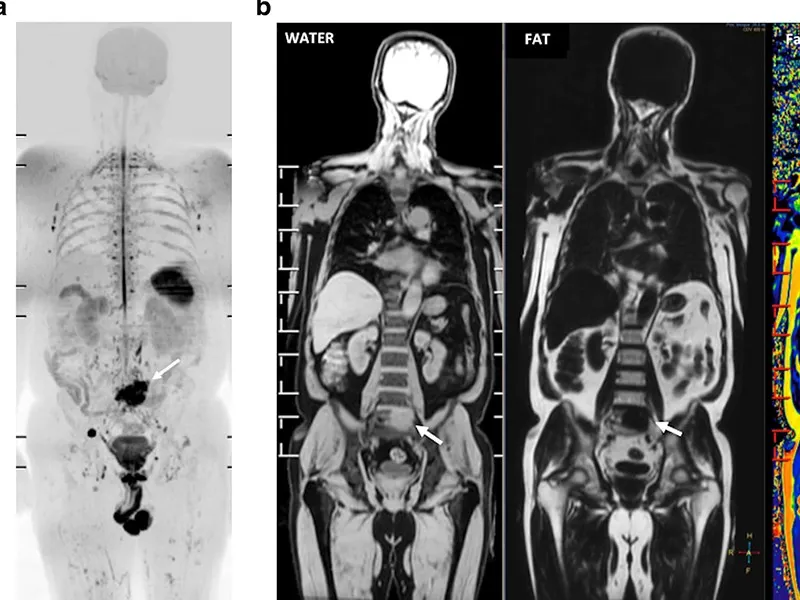

Tüm vücut MR, manyetik rezonans görüntüleme teknolojisi kullanılarak vücudun tamamının ayrıntılı bir şekilde taranmasıdır. Radyasyon içermeyen bu yöntem, manyetik alan ve radyo dalgaları yardımıyla organların ve dokuların yapısını detaylı bir şekilde gösterir. Doktorlar, bu görüntüleri kullanarak hastalıkları teşhis eder ve tedavi planlarını oluşturur.

Tüm vücut MR, genellikle hastalıkların erken teşhisi ve yayılımının değerlendirilmesi amacıyla çekilir. Özellikle kanser taramaları, inflamatuar hastalıklar, enfeksiyonlar ve dejeneratif hastalıkların tespitinde kullanılır. Ayrıca, vücutta mevcut olan anormalliklerin detaylı bir şekilde incelenmesi için de tercih edilir.

Tüm vücut MR ile kanser türleri, tümörlerin yayılımı, inflamatuar hastalıklar, enfeksiyonlar, dejeneratif hastalıklar, sinir sistemi bozuklukları ve damar hastalıkları teşhis edilebilir. Bu yöntem, özellikle erken teşhis gerektiren hastalıklarda büyük önem taşır ve doktorların doğru tedavi yöntemini belirlemelerine yardımcı olur.